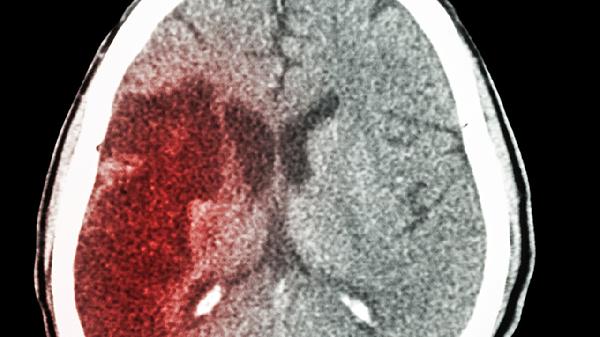

医生发现:每天慢走的脑梗患者,用不了多久,身体会有3大改善

每天散步20分钟,脑梗康复效果堪比"天然药丸"!神经科医生临床观察发现,坚持慢走的脑梗康复患者,身体会出现令人惊喜的变化。这些改变不是立竿见影的魔法,而是日积月累的生命礼物。

一、大脑悄悄发生的积极变化

1、神经通路重建加速

规律步行能刺激脑源性神经营养因子分泌,这种物质堪称"大脑肥料"。临床观察显示,坚持3个月的患者,核磁共振显示神经突触连接明显增多。